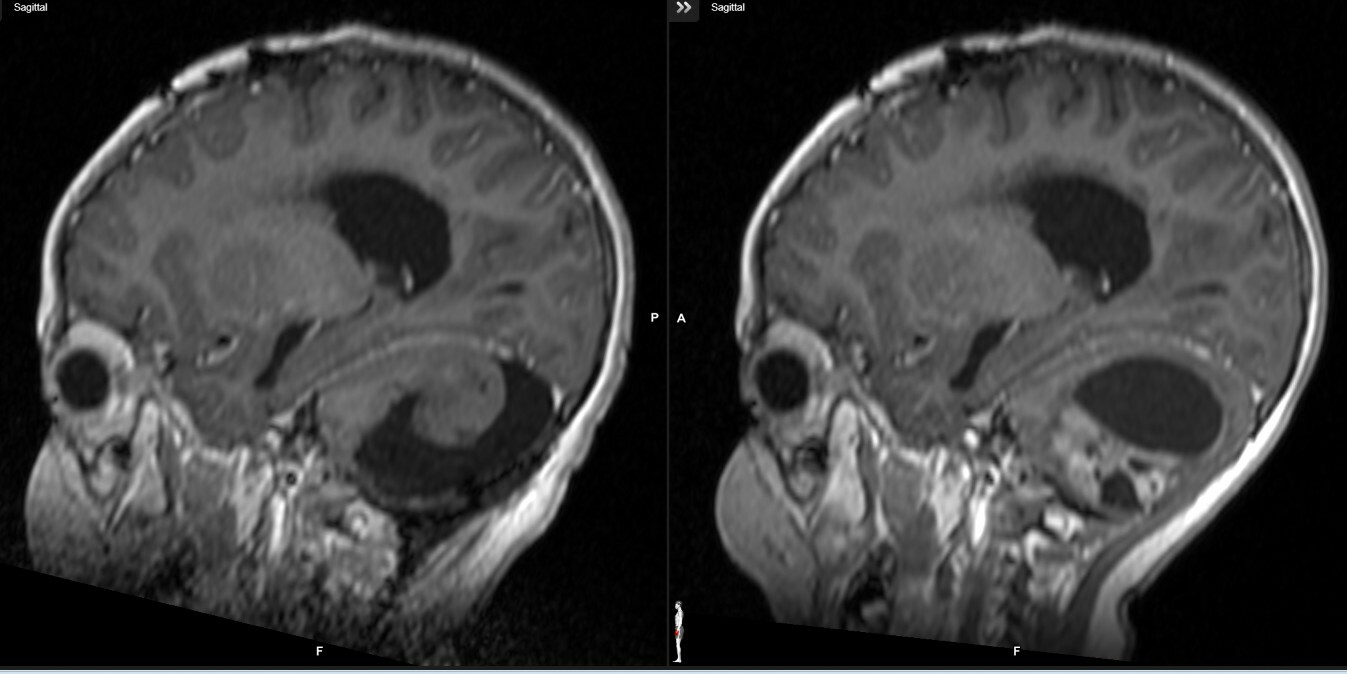

Η μετεγχειρητική MRI επιβεβαίωσε την πλήρη αφαίρεση του όγκου χωρίς υπολειμματική νόσο. Η ιστοπαθολογική εξέταση ανέδειξε πυλοκυτταρικό αστροκύττωμα (WHO Grade 1). Η πρόγνωση της ασθενούς κρίνεται εξαιρετική, με την πλήρη ίαση να είναι ο αναμενόμενος στόχος.